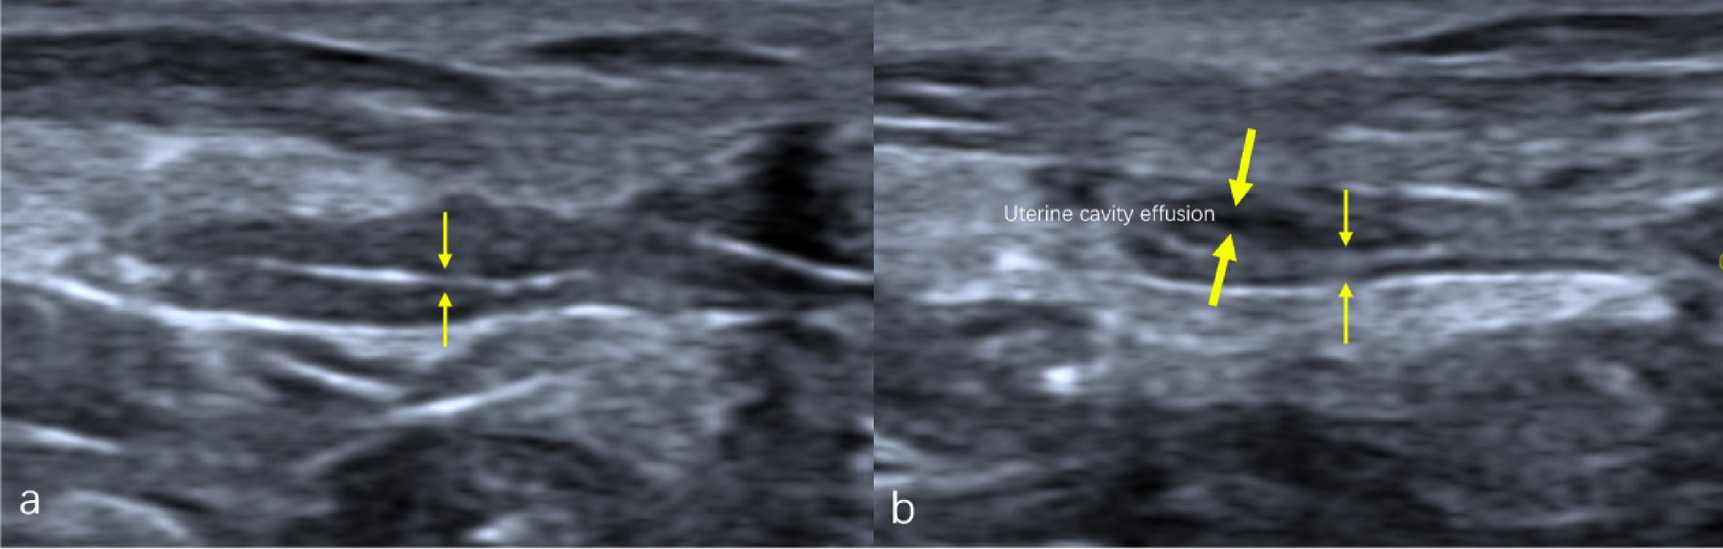

Fig. 8

Transabdominal ultrasound with the sagittal images demonstrating. Ultrasound image of the endometrium after modeling in the same rat (a) and ultrasound image of the endometrium after treatment with UC-MSCs (b). Endometrium (thin arrow), Uterine cavity effusion (thick arrow).